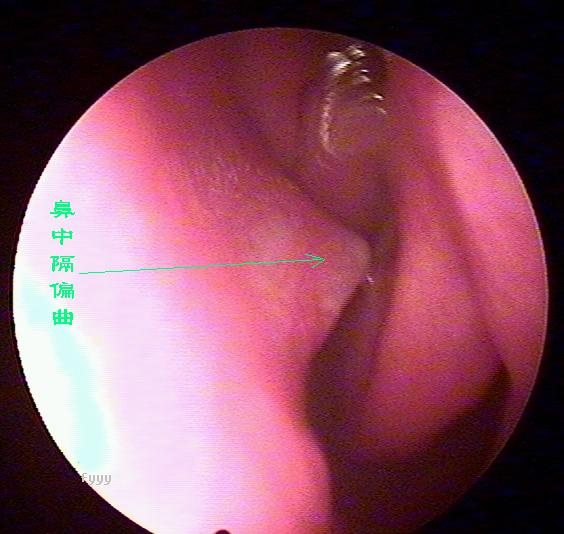

鼻中隔偏曲进行鼻内检查以判断鼻中隔偏曲的类型和程度,注意鉴别鼻中隔粘膜肥厚和是否同时存在鼻内其它疾病,如原发病变—肿瘤、异物或继发病变—鼻窦炎、息肉等。 另一罕见者为鼻中隔梅毒瘤,其质地中亦较硬,但该处粘膜明显充血。

“ 狼牌内窥镜”可通过耳鼻咽喉等部位狭小通道直接看到常规仪器检查所不能看到的病灶,并可放大数十倍甚至百倍,有助于清晰而详细地观察到周围的病变,只需要5分钟即可检测出疾病病因,辅助医师进行精准治疗,告别耳鼻咽喉疾病治疗误区,具有不易漏诊而精准治疗的优点,被业界称为耳鼻喉科医生的“只眼睛”。